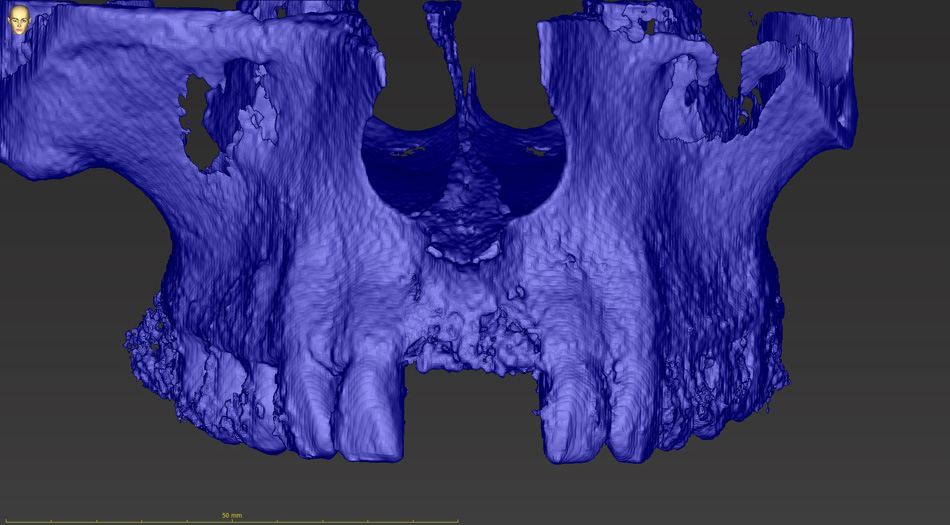

Lékař si vytvoří všechny typy zobrazení potřebných pro naplánování – tedy 2D snímky (panoramatický), příčné řezy i 3D model.

Vidí zde i důležité anatomické útvary – čelistní dutinu, průběh nervu atd. Po proměření množství kosti – šířky i výšky vybere z databáze vhodný typ implantátu a umístí ho do požadované lokality. Ihned vidí jeho pozici ve všech 3 rovinách a na všech snímcích i 3D modelu. Může upravovat podle potřeby jeho pozici, sklon atd.

Všechny vybrané a správně umístěné simulované implantáty se ukládají do „počítačové karty“ pacienta s jejich pozicí, délkou, průměrem, typem i sklonem. V programu také lékař navrhuje chirurgické šablony pro řízenou nebo navigovanou implantaci. Lékař i pacient tedy ještě před vlastní operací vidí, jak by mělo ošetření probíhat a vypadat.